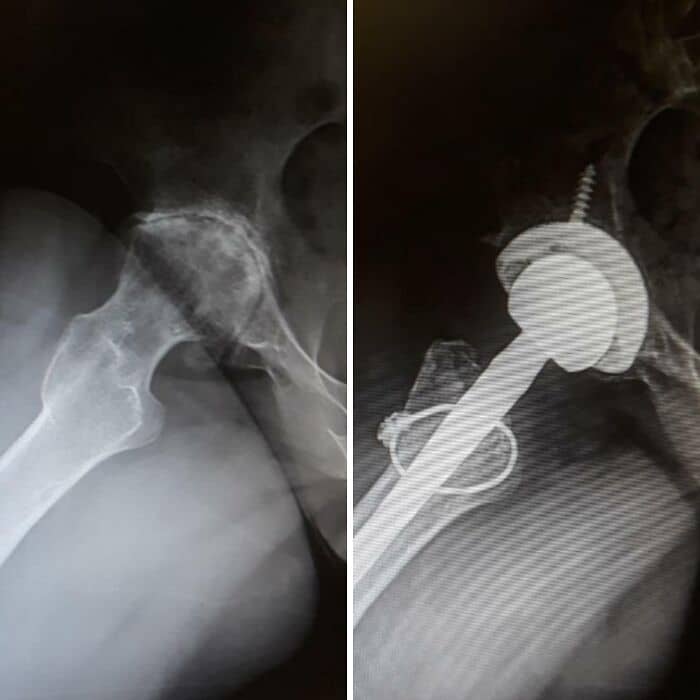

#10 These Are X-Rays Taken Before And After The Surgery

It has been 4 years to the day since I had my scoliosis surgery. The surgery itself took 14 hours. Surgeons drilled metal straightening bars into my spine.

#46 Before And After Hip Replacement Surgery